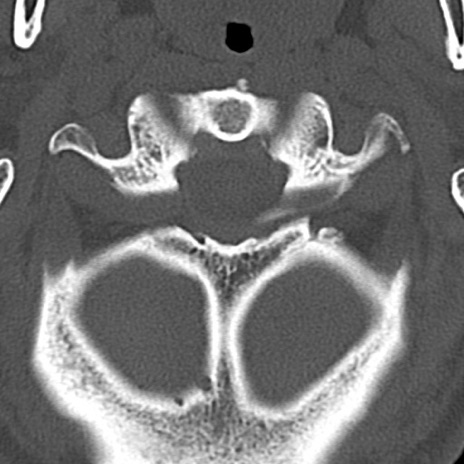

頚椎CT

横断像